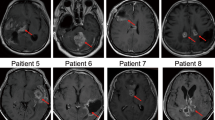

The pre- and posttreatment gene expression and pathway analysis results indicate that differences in viral permissiveness translate in differences in expression levels of genes mediating immune and inflammatory responses. We then sought to evaluate if this would translate in differences in the development of posttreatment immune infiltrates and tumor microenvironment remodeling. Eleven out of 13 patients in Group B had matched pre- and posttreatment (day 5) samples available for IHC analysis of immune infiltrates. There was a significant increase in CD8+ and CD68 + T-cell infiltration from baseline tumor samples to day 5 of treatment (CD8: Wilcoxon signed-rank test V = 57, P = 0.032, n = 11, Fig. 6A, B, CD68: Wilcoxon signed-rank test V = 56, P = 0.042, n = 11), but not of CD4+ cells (Supplementary Fig. 3A). There was a moderate negative correlation between lower DLDA score (i.e., increased permissiveness to viral replication) and a greater increase in CD4+ and CD8 + T cells following treatment (CD4: Spearman’s rho = −0.52, S = 334, P = 0.11; CD8: Spearman’s rho = -0.46, S = 322, P = 0.154, Fig. 6C and Supplementary Fig. 3B). A greater change in posttreatment CD4 + , CD8+ and CD20+ cell percentage was observed in patients who were not on corticosteroids at study entry (Wilcoxon rank-sum test CD4+ P = 0.042, CD8+ P = 0.024, CD20+ P = 0.042; Supplementary Fig. 2B).

A There was a significant increase in CD8 + T-cell infiltration from baseline tumor samples to day 5 of treatment (CD8: Wilcoxon signed-rank test V = 57, P = 0.032, n = 11). B Development of CD8 + T-cell predominant lymphocytic infiltrates was observed in study patients following one dose of MV treatment, including patients with intermediate DLDA scores. Representative examples of two study patients are shown. C Correlation between DLDA score and CD8 + T-cell increase following treatment. Spearman’s rho = −0.46 (95% CI: −0.83 to 0.19, two-sided P value, P = 0.154, n = 11 patients with available log2 fold change CD8 data). D Lymphocytic cell infiltration was evaluated in tumor specimens obtained in subsequent surgeries following study completion in a subset of study patients; evolution of the percentage of CD8-positive cells is depicted. Source data are provided as Source Data file.

Five of the 11 patients had additional surgeries performed at 1.3, 1.8, 4, 7.3, and 8 mo from study entry In 4 of 5 patients, lymphocytic infiltration had returned at or below baseline levels at the time of subsequent surgery, while in one patient the lymphocytic infiltration increased over time (Fig. 6D).